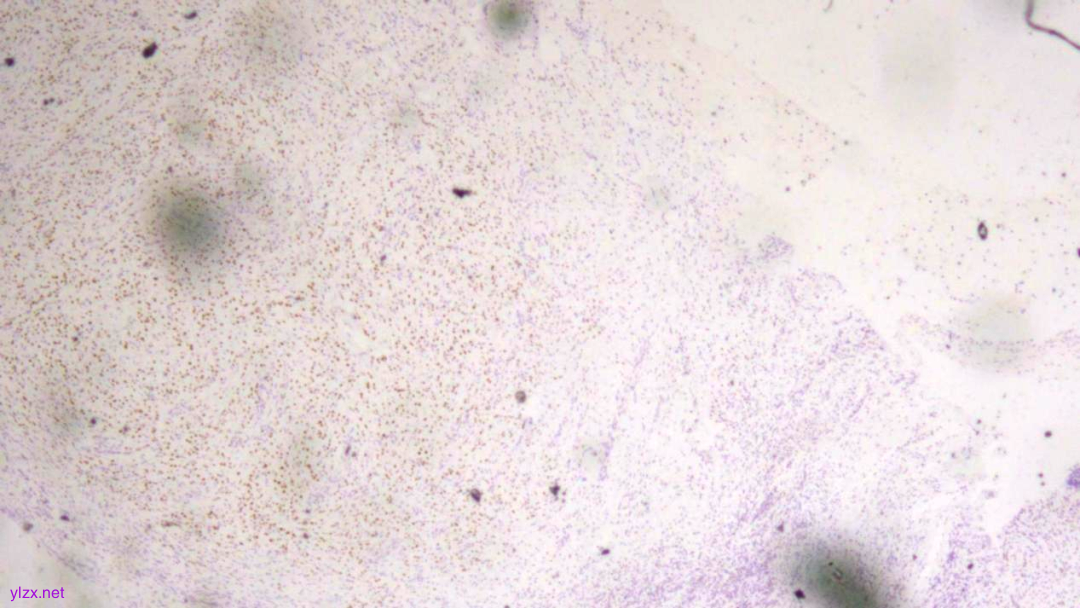

IHC结果:

CK(AE1/AE3)(+)、GATA3(+)、P120(浆+)、E-Cadherin(-)、CK7(+)、CK-H(+)、CAM5.2(+)、CK20(-)、CEA(poly)(-),P53(约40% 弱+),Ki-67(约1%+)

AE1/AE3(弥漫强+)

GATA-3(+)

P120(浆+)

E-Cadherin(-)

CEA(少量+)

CK7(弥漫强+)

ki-67(个别细胞+)

病理诊断:

(胃窦)腺癌,HE形态结合临床病史、免疫组化结果,符合乳腺浸润性小叶癌转移。